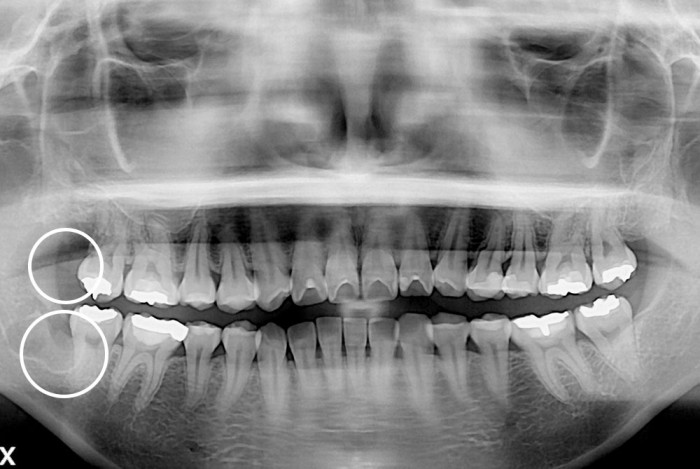

[사랑니] 사랑니

치료전 : 2019-10-16